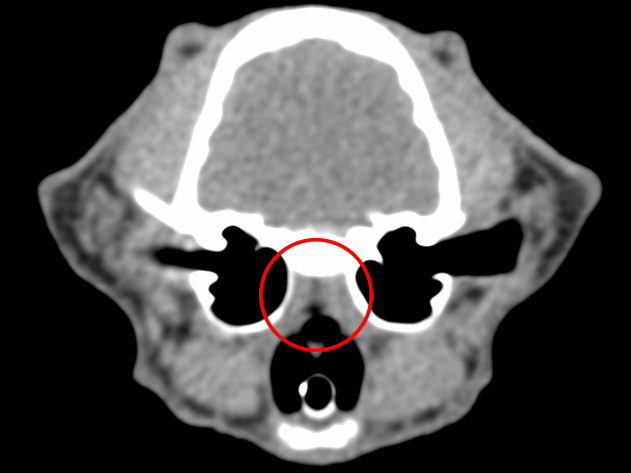

CT検査:赤丸が狭窄部位

約3ヶ月前より鼻炎症状を主訴に他院を受診し、鼻炎としての治療が行われたものの、十分な改善が見られなかったため、精査を目的として当院を受診されました。 当院にてCT検査を実施したところ、鼻咽頭部に顕著な狭窄を認めたことから、呼吸器症状の改善を目的に、鼻咽頭狭窄に対するバルーン拡張術を実施しました。 処置後の経過は良好で、全身状態も安定していたため当日退院としました。 その後も経過観察を継続しており、現在までに7ヶ月が経過しましたが、再発は認められていません。